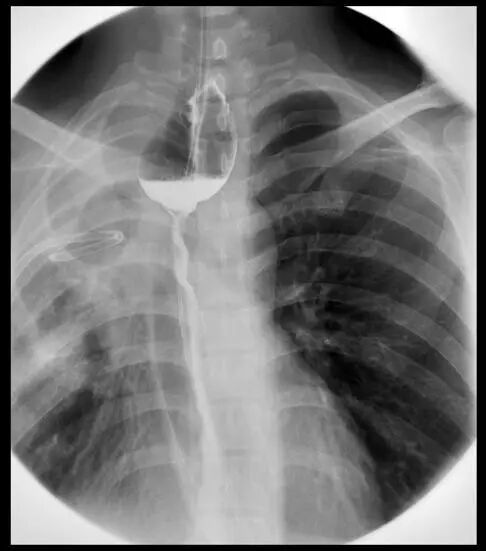

食管胃吻合口瘘

内镜夹怎么不掉CJP每周一帖--OTSC吻合夹系统在经内镜治疗消化道出血、穿孔及瘘中的应用_https://www.jmylbn.com_新闻资讯_第27张

内镜夹怎么不掉CJP每周一帖--OTSC吻合夹系统在经内镜治疗消化道出血、穿孔及瘘中的应用_https://www.jmylbn.com_新闻资讯_第28张

术后碘油造影,OTSC夹清晰可见,未见吻合口瘘患者术后1月和2月随访,进食可,未见不适